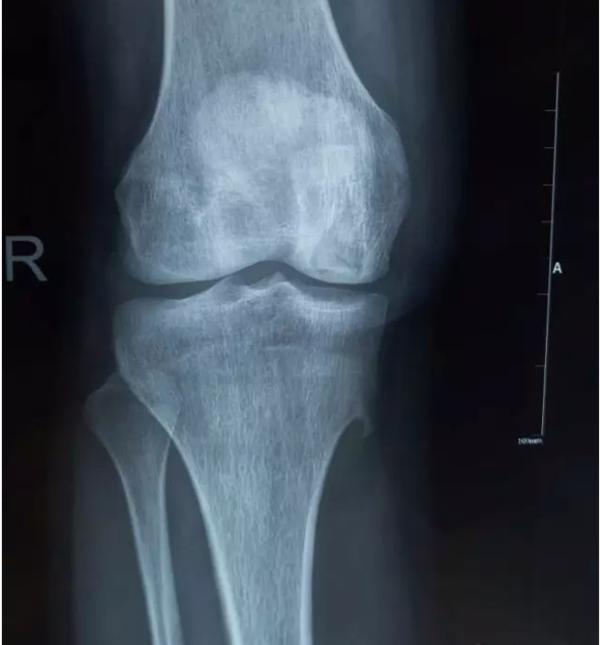

膝关节不均匀沉降术后患者X线片(下图)